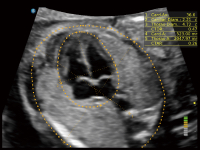

通过创新的Matrix E自适应滤波算法,能有效滤除软组织和噪声信号,最大限度保留超低速微细血流的信号;结合超长时间域算法,极大提升细微血流的敏感性和空间分辨率,更真实的反应组织、包块的血流灌注情况。